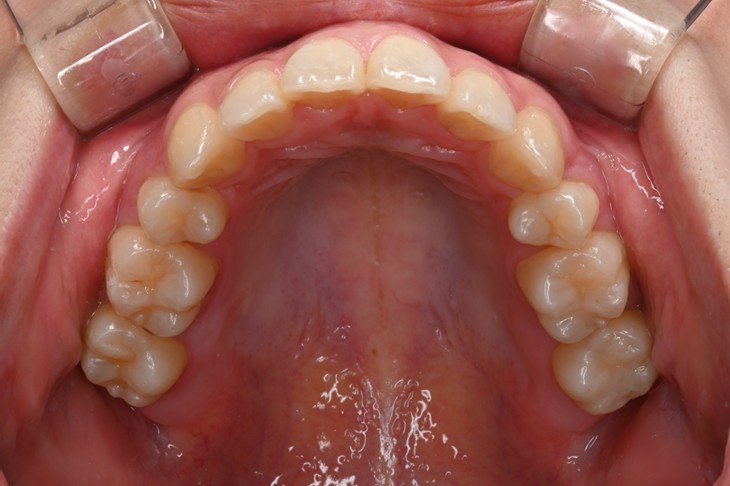

症例2:八重歯が気になる

| 患者様データ | 20代 女性 |

| 来院主訴 | 八重歯が気になる。 |

| 治療内容 | 八重歯を治すために上の親知らずを抜歯し、インビザラインにてマウスピース矯正を開始しました。かみ合わせを整えるためにゴムかけを行いました。 |

| 概算治療費 | 約85万円 |

| 治療期間 | 1年3ヶ月 |

| 通院回数 | 8回 |